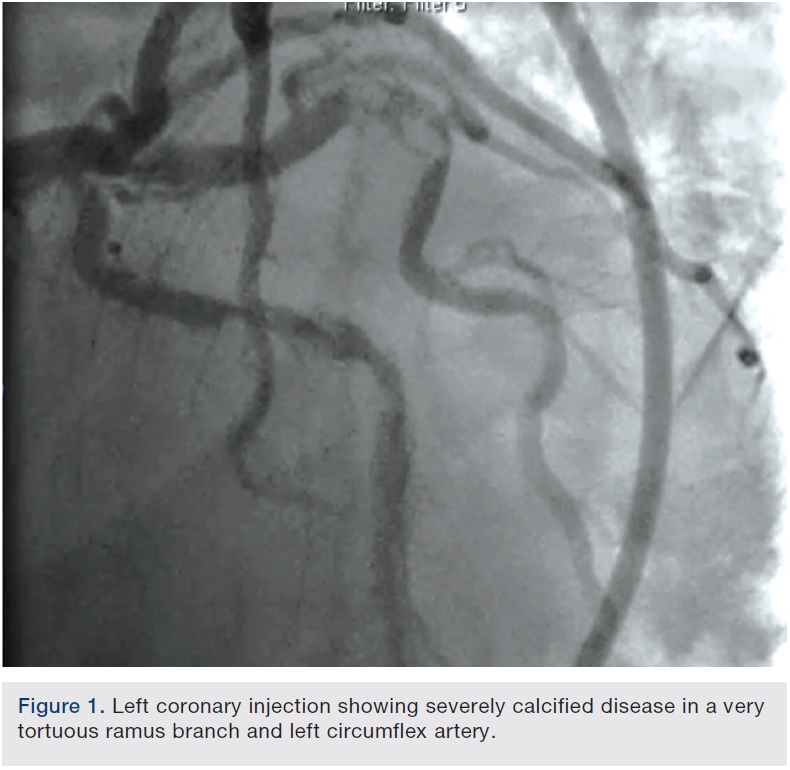

A 62-year-old man presented with chest pain and troponin leak. He had a history of end-stage renal disease on hemodialysis, critical limb ischemia status post left above-knee amputation, hypercholesterolemia, and ischemic colitis. He had also experienced a remote inferior infarct. His echo showed a newly decreased ejection fraction of 20%. Cardiac catheterization was performed, revealing a chronic total occlusion of the right coronary artery, and severe calcific obstructive disease in the left circumflex and ramus branch (Figure 1).